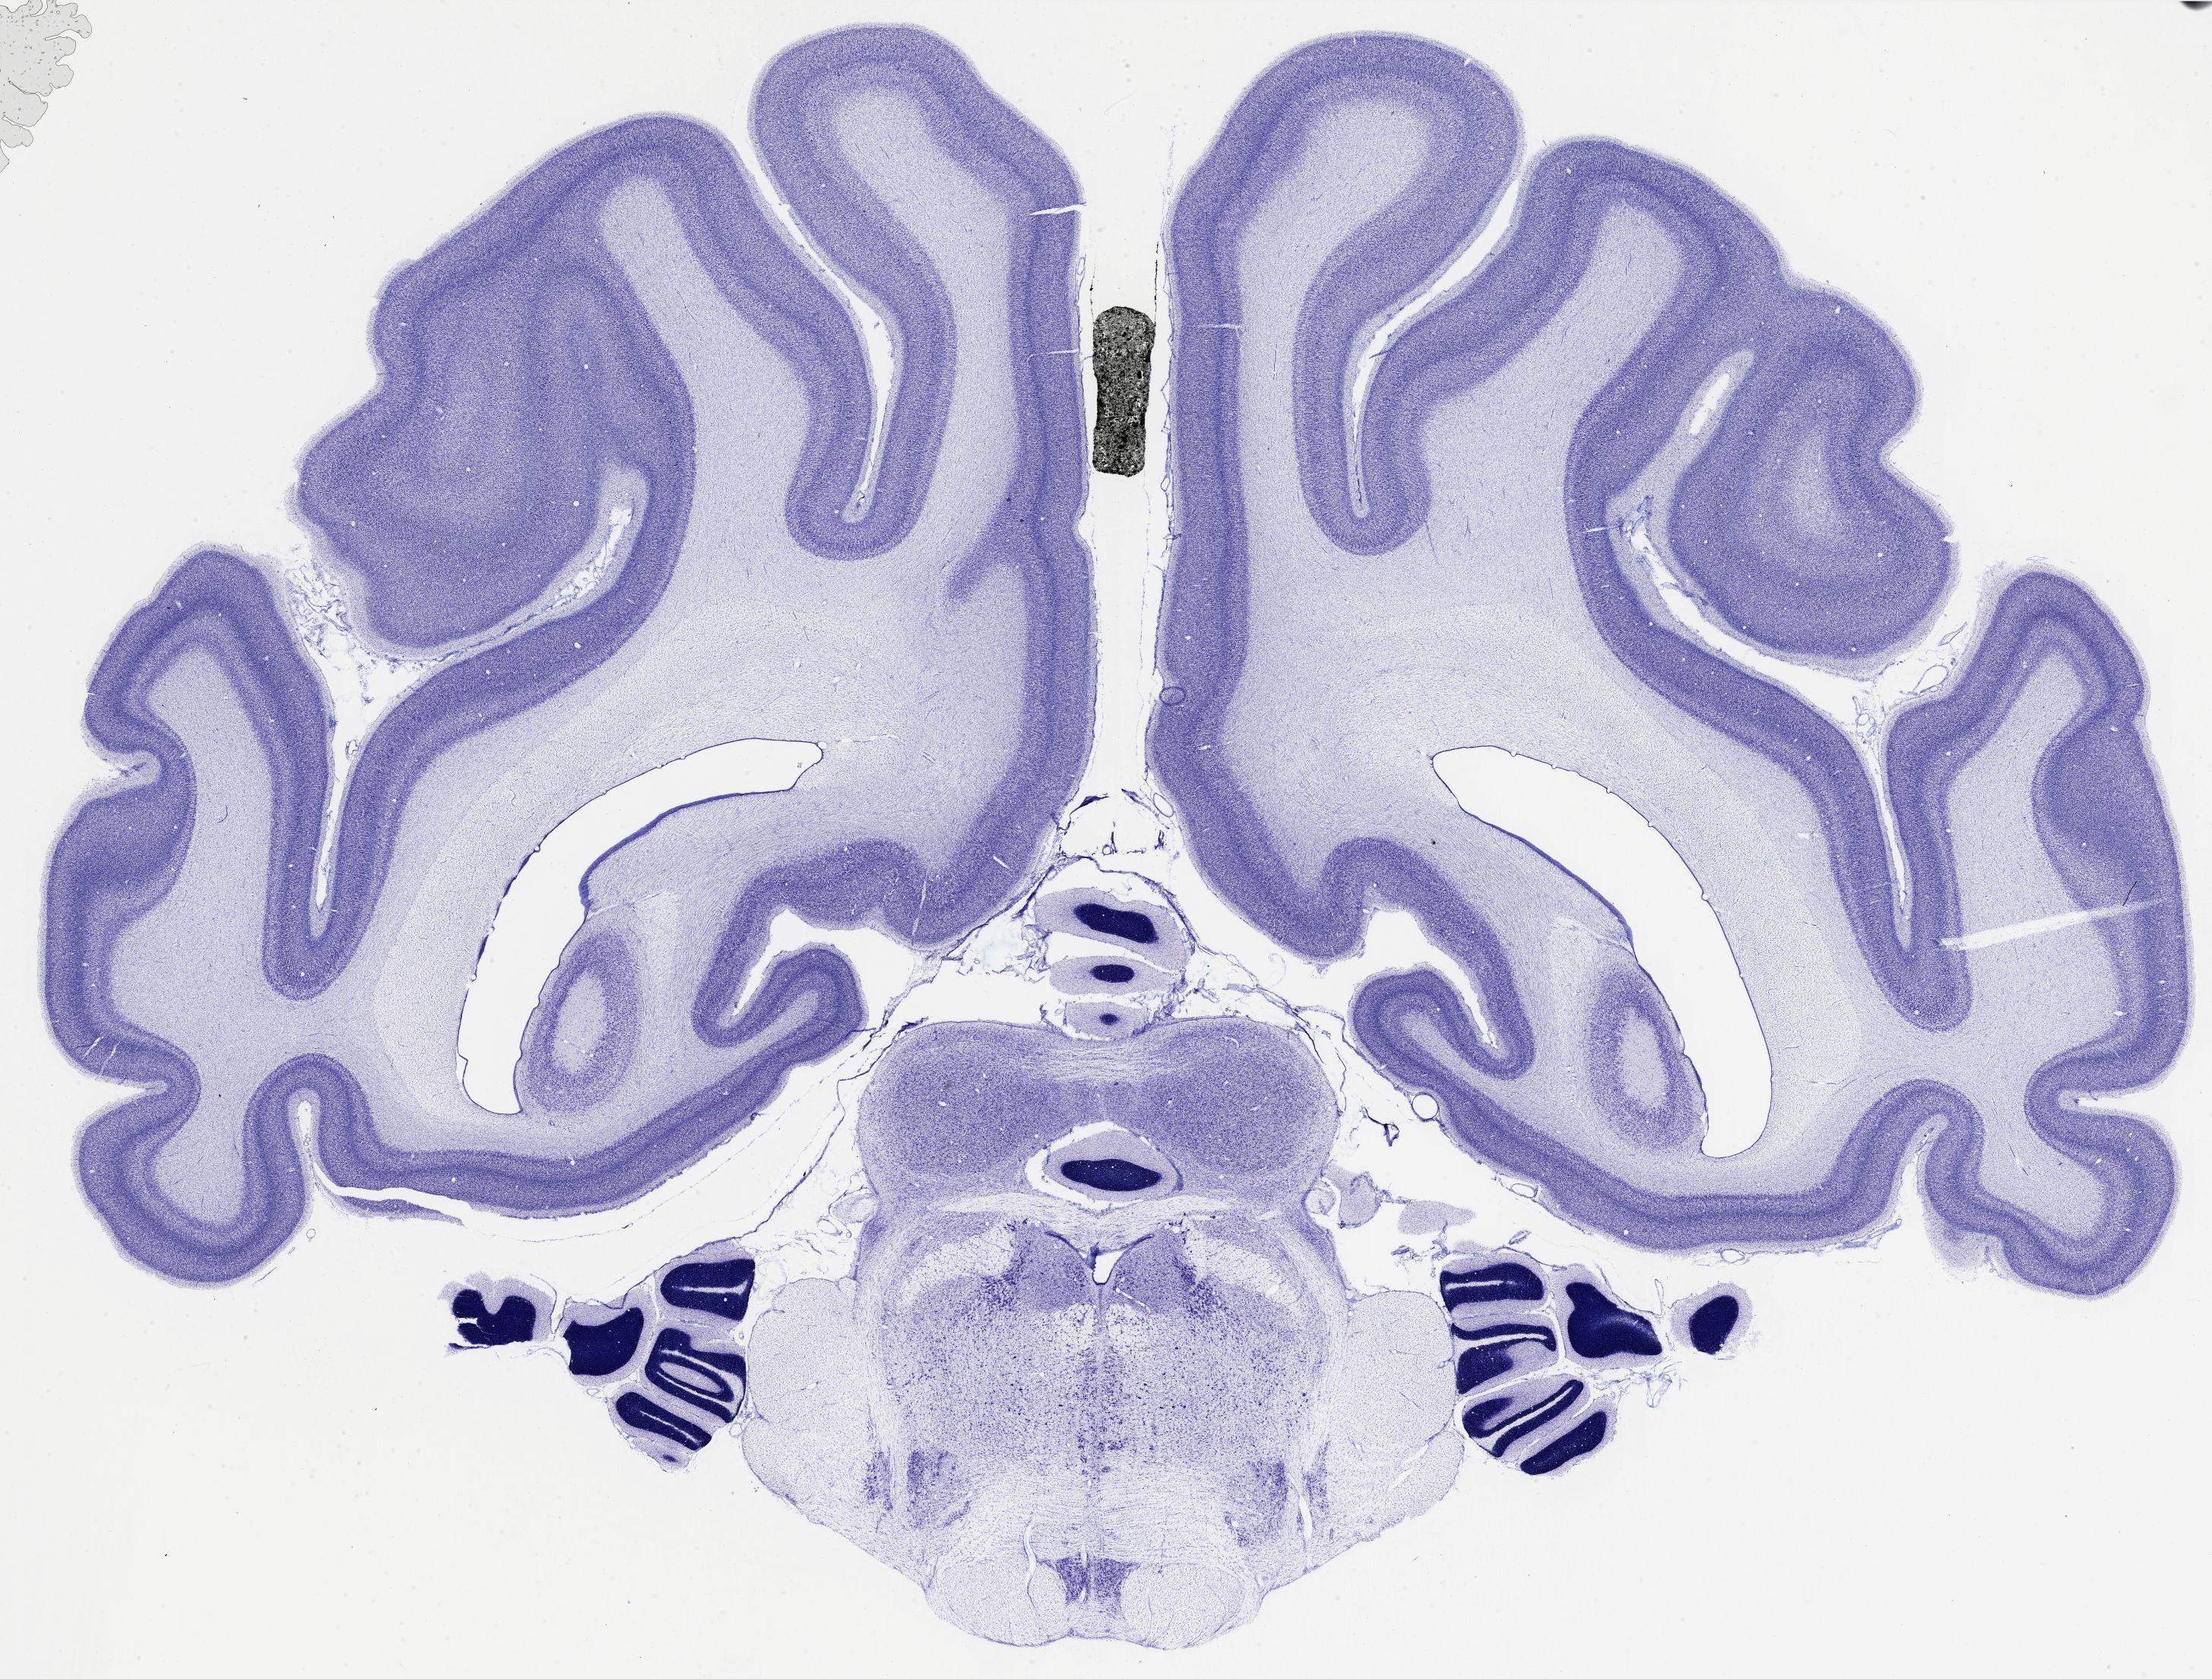

Datasets -> Chlorocebus Aethiops -> Nissl, coronal, histo, Whole-Brain, adult

[ Metadata ]   ·   Source: NeuroScience Associates

thumbnail

521